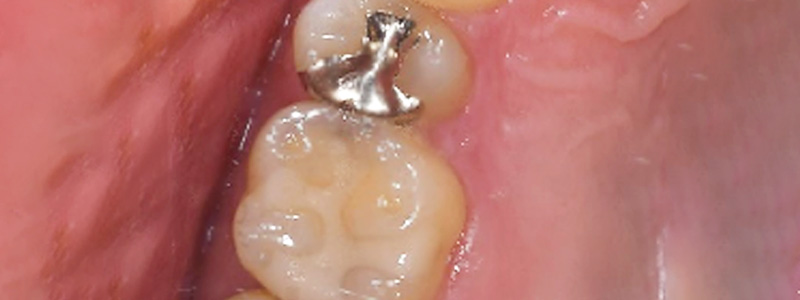

- 治療名

- セラミックインレー

- 治療内容

- 銀歯と隣の歯のむし歯治療を行い、共にセラミックインレーを装着。

- 患者様

- 50代女性

- 治療期間

- 2回

- 費用

- ¥132,000

- 治療に対するリスク

- 術後疼痛、冷水痛

- 執刀医

- Dr.村尾